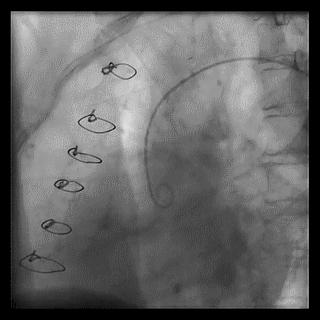

➢ CASE 5

升主动脉造影未见桥血管显影,原位血管造影也没发现竞争血流迹象,可以确定桥血管已闭塞,必要时可以借助冠脉CTA辅助诊断

(4)LIMA桥血管造影

首选导管:JR4.0导管

其他导管:如果开口明显成角应选用专用的内乳动脉造影导管

➢ CASE 6

经股动脉途径TIG,非选择造影如果能清晰显影,可不做超选造影

➢ CASE 7

经左侧桡动脉途径JR4.0,非选择造影如果能清晰显影,可不做超选造影